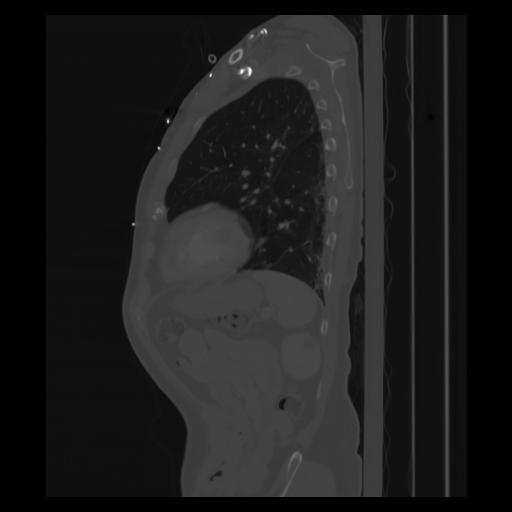

30 CUERPO,CE,Sagittal,3.000,CUERPO,Sagittal,